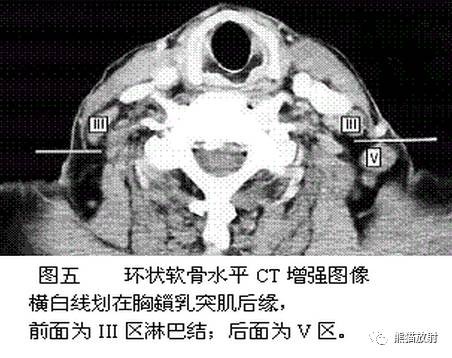

III区:颈内静脉链中组

V区:颈后三角区淋巴结,即胸锁乳突肌后缘、斜方肌前缘及锁骨构成的三角区内的淋巴结

舌骨水平CT增强图像

横白线划在胸锁乳突肌后缘。

白线前为III区淋巴结,后为V区淋巴结。